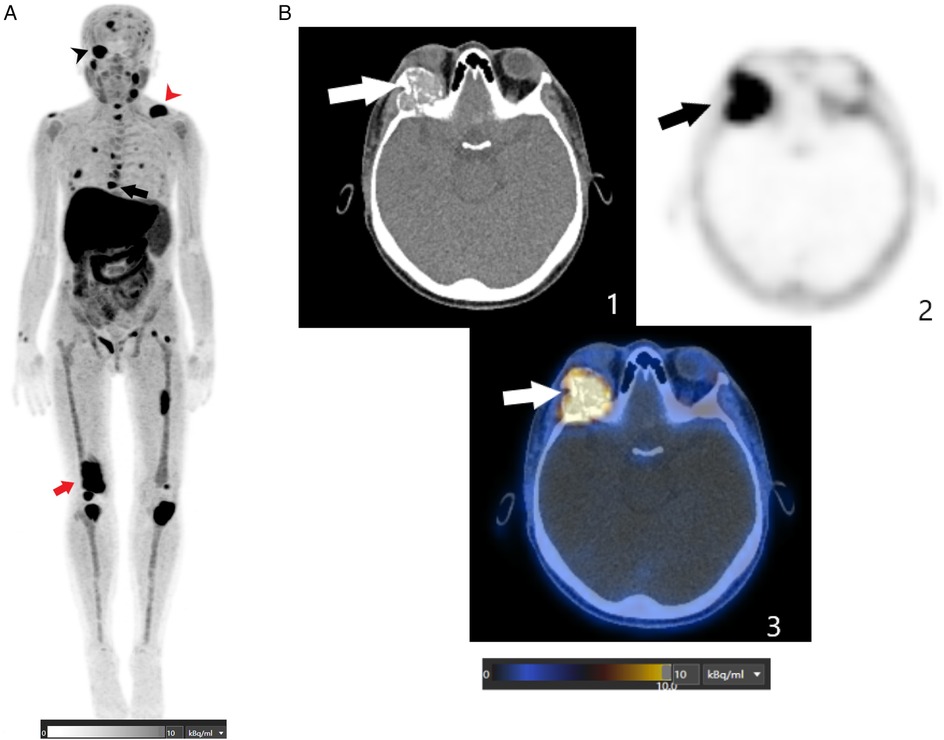

Beyond parathyroid localization, whole-body imaging revealed multiple FCH-avid skeletal lesions. Maximum intensity projection images showed widespread abnormalities throughout the skeleton. The most striking finding was a large hypermetabolic osteolytic lesion involving the right orbital roof and lateral wall, with extension into the orbital cavity, correlating directly with the patient's ocular symptoms. Additional tracer-avid lesions were observed in the mandible, cervical and thoracic vertebrae, ribs, pelvis, and long bones, including the femurs and tibias (Figure 2).

Figure 2

Composite image showing medical scans. Part A is a full-body scan with various black and red arrows indicating specific areas. Part B includes three panels: 1 shows a CT scan with a white arrow pointing to a highlighted area, 2 is a blurred scan with a black arrow, and 3 combines CT and PET imaging, highlighting an area with a white arrow. A color scale below indicates intensity.

Figure 2. (A) This FCH PET/CT MIP image shows multiple abnormal foci spread throughout the skeleton, including the axial and peripheral skeleton. The black arrowhead indicates a hypermetabolic osteolytic lesion involving the right orbital roof and lateral wall, extending into the orbital cavity. The red arrowhead indicates a lytic lesion in the left clavicle. The black arrow indicates a lytic lesion in the T8 thoracic vertebra. The red arrowhead indicates a lytic lesion in the right femur. (B) These axial FCH PET/CT images (1: CT image; 2: PET image; and 3: fusion image) are centered on the orbits and show an intense FCH-uptake osteolytic lesion (SUVmax of 13.2) involving the right orbital roof and lateral wall and extending into the orbital cavity (depicted by the arrows).